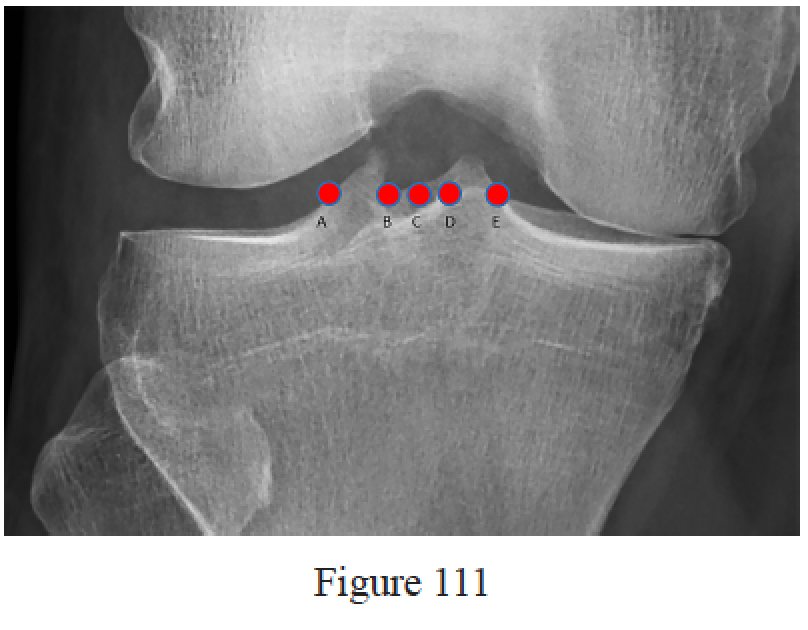

Gardner MJ, Yacoubian S, Geller D, Pode M, Mintz D, Helfet DL, Lorich DG. Prediction of soft-tissue injuries in Schatzker II tibial plateau fractures based on measurements of plain radiographs. J Trauma. 2006 Feb;60(2):319-23; discussion 324. PubMed PMID: 16508489.

Gardner MJ, Yacoubian S, Geller D, Suk M, Mintz D, Potter H, Helfet DL, Lorich DG. The incidence of soft tissue injury in operative tibial plateau fractures: a magnetic resonance imaging analysis of 103 patients. J Orthop Trauma. 2005 Feb;19(2):79-84. PubMed PMID: 15677922.